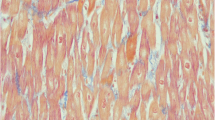

A 7-month-old boy from Guyana was transferred to our unit after diagnosis in his native region of cardiomyopathy. He was born at term, after a normal gestation, from nonconsanguineous parents. He had 2 healthy brothers and a third brother who died at 5 years of age in a context of pulmonary disease. In our patient, a systolic murmur found during neonatal physical examination first led to the diagnosis of an asymptomatic ventricular septal defect, which subsequently closed spontaneously. At 6 months of age, because of the recurrence of a systolic murmur, he underwent, in Guyana, a cardiac ultrasound examination that confirmed a closed ventricular septal defect but revealed left ventricular failure. The patient was secondarily transferred to La Timone Enfants Hospital in Marseille (France). On physical examination, the patient presented with well-tolerated tachycardia (160 beats per minute) and with a moderate hepatomegaly (2 cm below the costal margin). Growth and psychomotor development were normal. Cardiac ultrasound showed normal anatomy but a dilated, hypokinetic, and hypertrophic left ventricle: ejection fraction 18% (normal >60%), shortening fraction 8% (normal >30%), end-diastolic left ventricle diameter 43 mm (z-score +7.9), and end-diastolic intraventricular septal diameter 7.3 mm (z-score +3.9). Laboratory testings revealed a normocytic hypochromic nonregenerative anemia (hemoglobin levels: 69 g/L, mean globular volume: 75 fl, mean corpuscular hemoglobin: 24 pg, reticulocytes: 54 Giga/L) and cytolysis (aspartate aminotransferase: 170 IU/L, alanine aminotransferase: 98 IU/L) without cholestasis. Blood electrolytes, urea, and creatinine were normal. Plasma amino acid chromatography was normal and urinary organic acid profile revealed a moderate and transient dicarboxylic aciduria. Plasma carnitine was severely reduced (in various samples: free carnitine: 1–3 μmol/L, total carnitine: 2–4.5 μmol/L). A carnitine transporter defect was suspected and confirmed by the study of l-[methyl-3H] carnitine uptake by fibroblasts (according to Treem et al. [11]). Treatment with carnitine was started as soon as samples for laboratory testings were taken (and thus before confirmation of diagnosis), intravenously at 185 mg/kg per day for 6 days and then orally at 145 mg/kg per day. The child tolerated PO intake. Oral carnitine supplementation was then progressively increased because of the persistence of low plasma carnitine levels. It was increased up to 215 mg/kg per day divided in 3 doses, with the same dose in the morning and in the afternoon and a higher dose at night so as to maintain stable levels. The patient was concomitantly started on diuretics (spironolactone, furosemide), β-blockers (carvedilol) and an inhibitor of angiotensin I-converting enzyme (captopril). He underwent blood transfusion because of the severity of the anemia in the context of cardiomyopathy. Iron supplementation was also started. Cardiac function clearly and rapidly improved while on treatment (Table 1). Four months after starting the treatment, the patient was allowed to go back to Guyana with his family, where local doctors will continue treatment.

Carnitine transporter defect is a rare but treatable etiology of metabolic cardiomyopathy. Over half of the known cases of carnitine transporter deficiency first presented with progressive heart failure and generalized muscle weakness [7]. Tein et al. described the features of 11 cases of primary carnitine deficiency [10]. Cardiomyopathy was present in all cases. A prompt response to carnitine therapy occurred in 8 cases within the first month of therapy. Of the remaining 3 children, 2 died during an acute episode before diagnosis was made and therapy started. In the last child, the diagnosis was made at 3.5 months when cardiac features were limited to mild echocardiography abnormalities; thus, the clinical response to treatment was difficult to evaluate in this asymptomatic child. Those data as well as our case report highlight the need to look for this disease in children with cardiomyopathy and the necessity to start treatment very early, even before receiving the results of blood sampling if suspicion is high. As shown by Tein et al. [10] and in our patient, rapid improvement of ventricular function can be obtained with appropriate treatment. The therapeutic effect of high-dose oral or intravenous carnitine supplementation may be the result of a passive diffusion of carnitine or an uptake by alternative lower affinity organic cation/carnitine transporters on the plasma membrane [9]. Our patient, after 6 days of high-dose intravenous carnitine therapy, required high oral doses unequally distributed over the day with higher doses at night, in order to achieve satisfactory plasma levels. This is consistent with literature data recommending intravenous therapy of 100–400 mg/kg per day of carnitine during life-threatening events, and for chronic treatment 100–300 mg/kg per day of oral carnitine [6]. In addition to cardiomyopathy, our patient presented with normocytic hypochromic nonregenerative anemia. In the literature, anemia was noted in 6 cases of primary carnitine transporter deficiency [10]. The red blood cell morphology on smear was variable: hypochromic, normochromic, normocytic, or macrocytic. The investigations made to search for an underlying etiology were negative in these 6 described patients. Carnitine is known to have a role in red blood cell metabolism: it stabilizes the cellular membrane and raises the red blood cell osmotic resistance [2]. Iron metabolism is also linked to carnitine because various authors showed low serum carnitine concentrations in healthy children with iron deficiency anemia [1, 8]. Thus, anemia may be present in carnitine transporter deficiency and an iron deficiency may worsen anemia in this context. Moreover, iron deficiency may be a cause of secondary carnitine deficiency (with moderately low plasma carnitine levels). In our patient, the hemoglobin level remained stable after transfusion, while he was receiving iron and carnitine therapy. Although it was not clear, iron deficiency was probably associated with his primary carnitine deficit (normal ferritinemia but low siderophilin saturation were present).